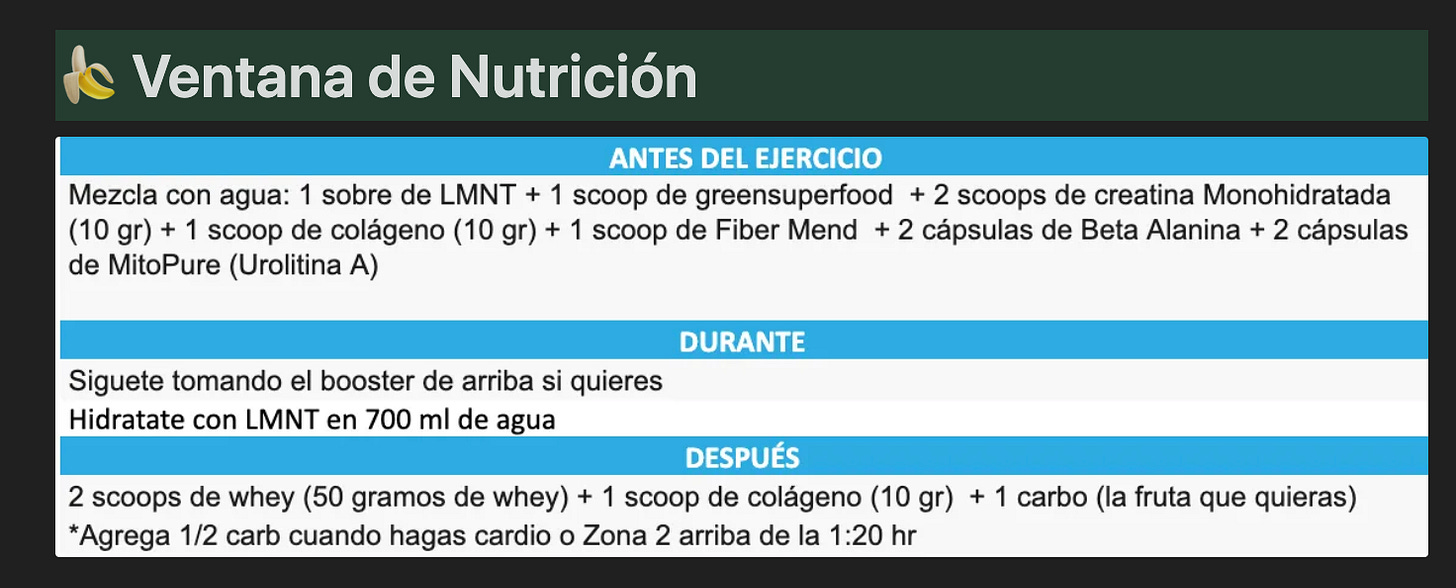

Género: Femenino + Edad 50 años + Estatura: 1.51 cm

Objetivos:

Bajar de grasa y subir de masa muscular.

Su problemática:

Resistencia a la leptina e insulina.

¿Que le puede mermar este proceso?

Su transición a su post-menopausia (declive hormonal)

Y revertir sus resistencias

¿Cómo se ven los resultados del inbody?

En cuestión de 5 meses bajo como 5% de grasa.

La masa muscular no se movió mucho porque le costaba llegarle a su proteína y le costo moverse de lugar con el tipo de pesas a llevar a cabo estaba muy atada a un entrenador desde hace años y no quiso que yo le llevara su fuerza. Y en lo personal a mi no me gustaba como le bajaba su entreno porque no era el adecuado para su etapa hormonal, edad y objetivos.

¿Cuál es su estrategia de alimentación?

¿Cómo esta ordenado lo que tiene que comer antes, durante y después de su ejercicio?

Normalmente prefiero utilizar proteína de suero (whey aislada o hidrolizada) post-entreno pero ciertos pacientes salen intolerantes a la whey en exámenes de intolerancias alimentarias IgG por lo que por eso usamos de carne.

Conclusiones de su caso y acciones a seguir llevando a cabo:

Enseñarle a cargar pesado poco a poco y emplear sobrecarga progresiva.

Que siga buscando llegarle al gramaje a su proteína animal.

Trabajamos un protocolo de suplementación específica para revertir leptina e insulina.